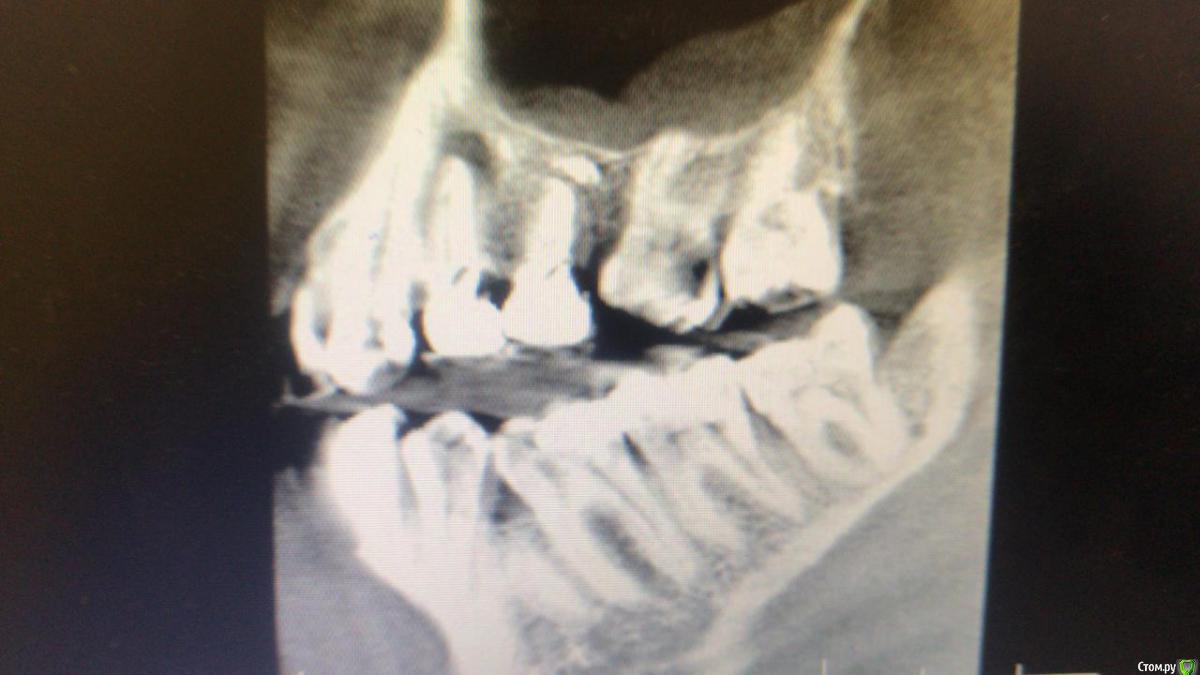

red_butler Опубликовано 18 июля, 2020 Поделиться Опубликовано 18 июля, 2020 Снимки не информативны Ссылка на комментарий

Александр9 Опубликовано 19 июля, 2020 Автор Поделиться Опубликовано 19 июля, 2020 Снимки не информативнымне сделали 3d снимки на аппарате FOMA, и скинули с программой для просмотра на флешку. Но на моем компьютере она не открывается (вот еще рентген есть Ссылка на комментарий